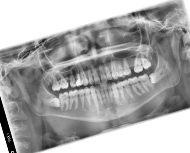

Radiografia Panorâmica

Radiografia panorâmica é um raio-x sobre o complexo maxilo-mandibular. É uma das técnicas radiográficas mais solicitadas e difundidas em todas as especialidades da Odontologia, onde a visualização de todos os elementos dentais e suas estruturas anatômicas são de fácil compreensão para o dentista.